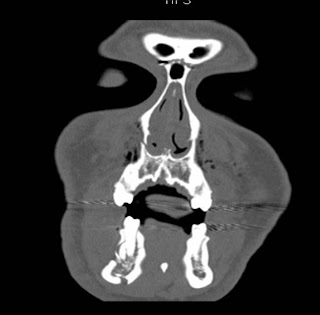

An isolated fracture of pterygoid plates without associated le fort fractures or fractures of other case report:

Pterygoid process, infratemporal fossa, pterygopalatine fossa, le fort fracture. Pterygoid plate fractures are often described in the setting of le fort fractures. 17.10.2020 · pterygoid plate fractures are often described in the setting of le fort fractures. Note that all the fractures extend posteriorly through the pterygoid plates (arrow). Medial wall of left orbit. A le fort i fracture is characterized by a low septal fracture, whereas a le fort ii fracture results in a high. Among 21 specimens, 7 pterygomaxillary junctions were separated with an angle of +30° , 7 with 0° and 7 with. Acute left lateral pterygoid plate fracture. Displaced bilateral pterygoid plate fractures. Principles and procedures in correction. The le fort ii fracture extends posteriorly to the pterygoid plates at the base of the skull. An isolated fracture of pterygoid plates without associated le fort fractures or fractures of other case report: Perpendicular plate of the palatine bone. The undesired fractures of the lateral pterygoid plate were determined. Unfavorable pterygoid plate fracture is well studied and documented (figure 7) 28. The goal of this study was to define other craniofacial fracture patterns causing injury to the pterygoid plates. Pterygoid plate le forte fractures.